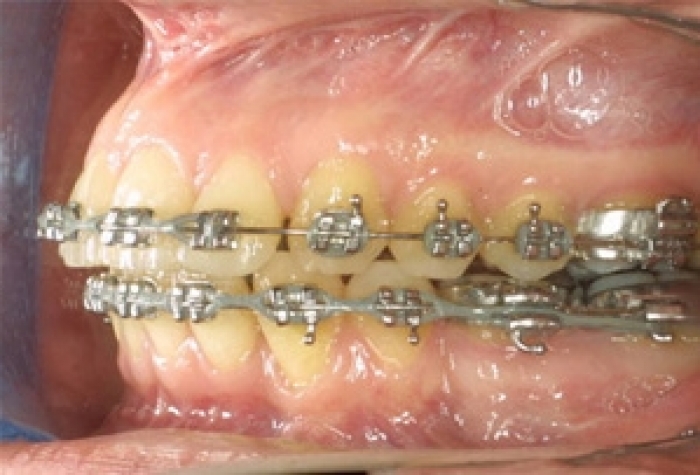

Mordida inicial